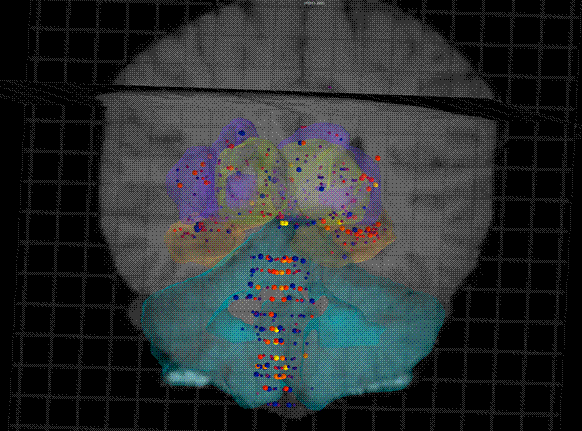

科学家将相关数据编制成一个名为“艾伦人脑图谱”的数据库,该图谱除了显著标识出人类基因图谱中的每个基因在大脑的何处表达之外,还涵盖了大脑核磁共振成像(MRI)和磁共振弥散张量成像(DTI)提供的数据,供公众自由免费访问。这些数据显示,人脑之间的相似度高达94%,至少82%的人类基因都会在大脑中表达。

与高性能、多功能的全球定位系统(GPS)一样,艾伦人脑图谱确定了人脑中的1000个解剖点,指明了每个点上特定的基因表达和基本的生物化学特性。科学家能借用艾伦人脑图谱探测人脑,厘清人脑遭受的疾病和损伤(包括生理损伤和精神健康疾病)对大脑特定区域的影响。科学家有望借此准确定位出某种特定的药物应作用于大脑的哪个区域并最终更好地控制很多疗法的治疗结果。